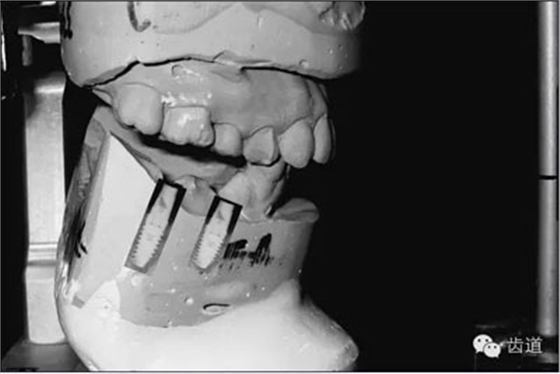

圖13:VF軟件指導下完成的模型上HE架

VF軟件也可以記錄上下頜之間的咬合關系,這對于將模型精確的上HE架很重要,所以對于復雜的種植病例(圖15),VF軟件也可以勝任將HE關系轉移至HE架的工作。HE架上的模型位置精確,種植體植入的位置和角度才能準確(圖16)。